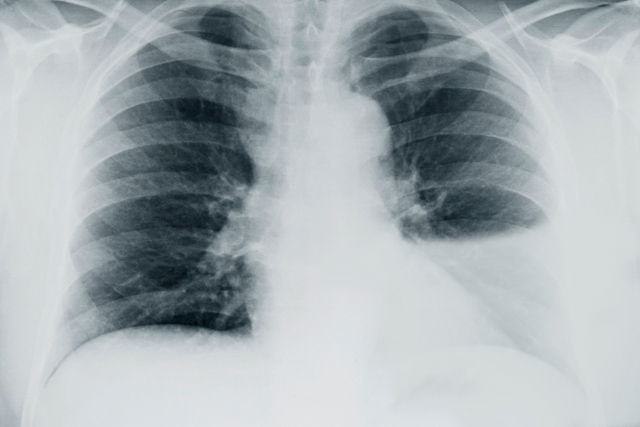

pleural effusion on chest x-ray

Raio X com derrame pleural do lado esquerdo

Pleural effusion is usually diagnosed by a primary care provider or a pulmonologist. The diagnosis is based on symptoms, medical history, and a physical exam. According to the American College of Radiology (ACR), a chest X-ray is the recommended first imaging test when pleural effusion is suspected because it can show the fluid as a lighter (whiter) area on the image.